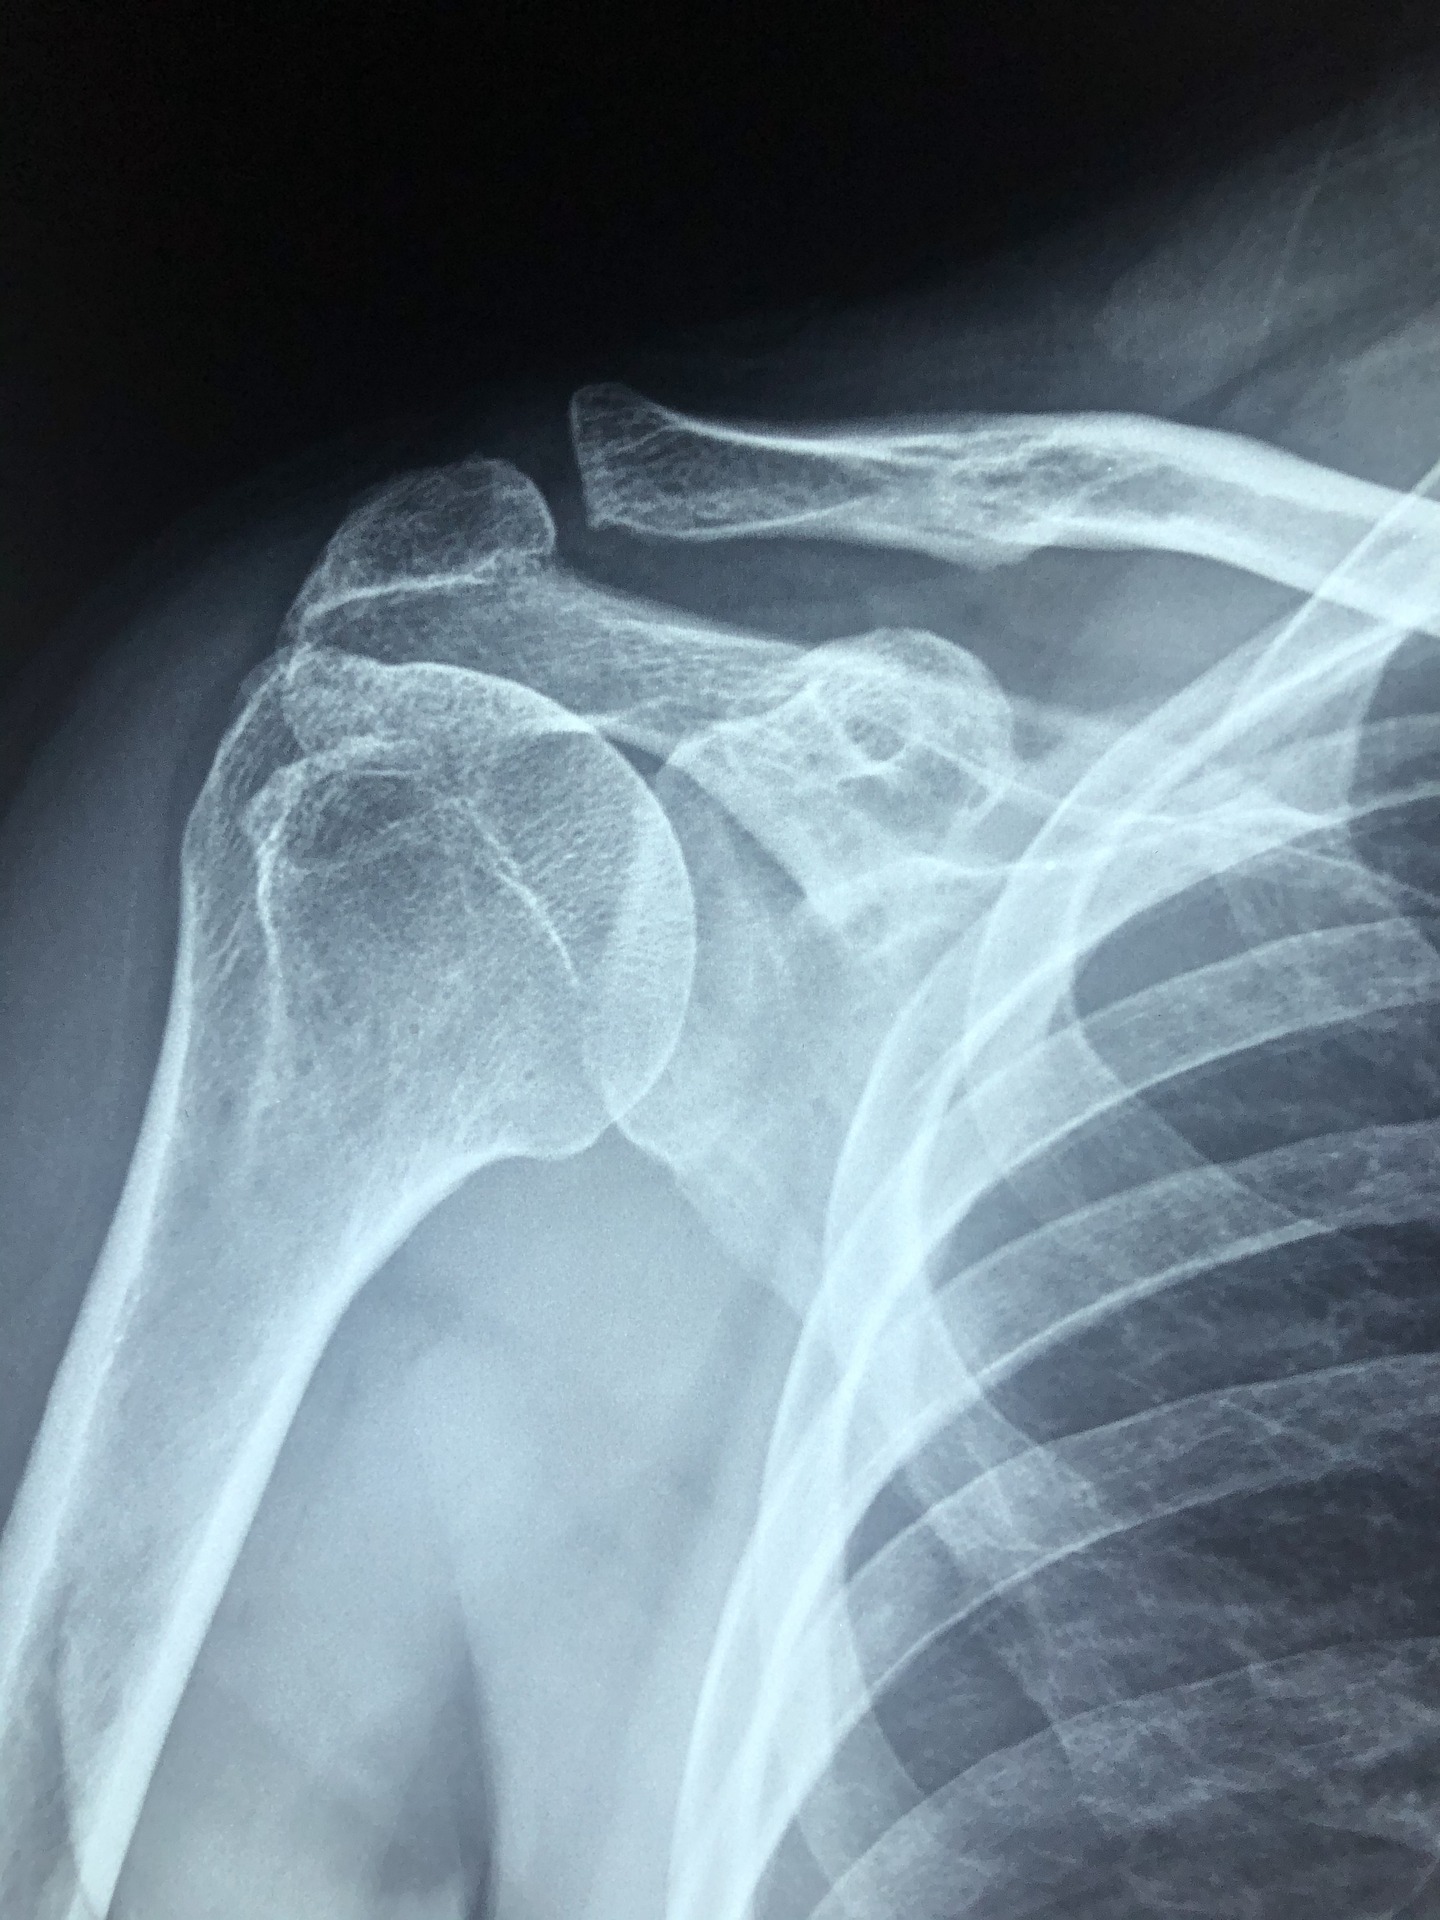

오십견이란 50세 전후로 나타나는 어깨통증성 질환을 부르는 말입니다.

속칭 굳은어 깨라고 표현하기도 합니다.

40, 50대에 접어들면서 어깨관절 주위 조직의 염증으로 활동에 이상이 생겨 발생한 질환으로

동결견, 유착성 관절낭염, 어깨관절주위염이라고 불립니다.